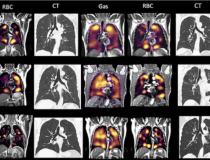

This photo gallery shows the variety of radiological presentations of COVID-19 (SARS-CoV-2) in medical imaging, including computed tomography (CT), radiograph X-rays, ultrasound, echocardiograms and magnetic resonance imaging (MRI). The radiology images show examples of typical COVID pneumonia in the lungs and the numerous complications the virus causes in the body in multiple organs, including the brain, kidneys, heart, abdomen and vascular system.

Ultrasound, especially hand-held ultrasound imaging devices, have become a primary imaging modality for novel coronavirus because of the ease to bag the device and sterilize it after use. CT and mobile X-ray systems are also used as front-line imaging systems for COVID-positive or suspected COVID patients.